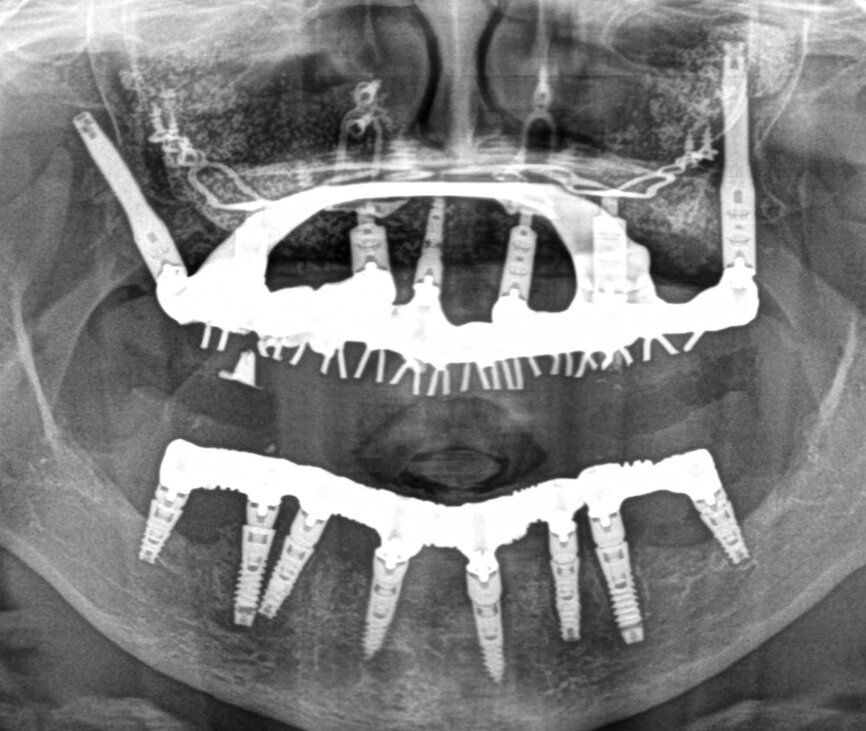

Au cours du temps, et avec la perte de l’organe dentaire, la crête alvéolaire va subir des modifications importantes, perdant progressivement sa hauteur, son épaisseur et sa densité. Lorsque la fonte osseuse se poursuit, l’osalvéolaire disparaît en quasi-totalité, laissant place à l’os basal qui constitue la structure matricielle de la face. Il ne reste que les piliers de la face essentiellement constitués d’os cortical : les piliers ptérygoïdiens, les piliers zygomatiques, les piliers canins et l’épine nasale. C’est à ce moment que l’implantologie basale prend tout son sens car cette discipline qui permet le plus souvent la mise en charge immédiate d’un bridge coulé vissé métal/résine, autorise une réhabilitation et une reprise fonctionnelle rapides en moins de quatre jours, (Fig 1)

Pour cela, elle fait appel à des implants spécifiques (Diskimplant : (Fig 2a, b)) permettant un ancrage dans l’os basal de la face, non soumis à la résorption, ainsi qu’à des techniques issues de la chirurgie maxillo- faciale.

Fig. 1 bridge coulé vissé métal - résine

Fig 2a : Implant spécifique : Diskimplant (Photo EPSON)

Fig.2b : implant spécifique : Diskimplant (Photo : EPSON )

Fig.2c : Implants à plaque et des implants axiaux spécialisés ptérygoïdiens Fratex

L’implantologie basale ne se limite pas aux seuls Diskimplants mais comprend également les implants à plaque et des implants axiaux spécialisés (ptérygoïdiens,Fratex : Fig 2c).